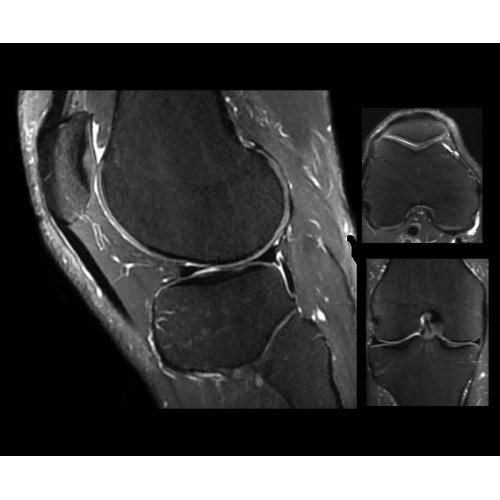

SIGNA PET/MR 3.0T — это гибридная система, в которой совмещаются две принципиально разные технологии — магнитно-резонансную томографию (МРТ) и позитронно-эмиссионную томографию (ПЭТ). Система отличающийся высокой чувствительностью и эффективностью и предназначена для диагностики в области онкологии, неврологии, кардио-васкулярных исследований, исследований воспалительных процессов.

Компания GE Healthcare представляет революционную, полностью интегрированную систему SIGNA PET/MR1, в которой сочетаются времяпролетная технология (TOF) и возможности напряженности магнитного поля 3.0 Тл. Мы поможем вам поднять исследования на более высокий уровень. SIGNA PET/MR позволяет достичь впечатляющей точности и скорости исследований, а благодаря новейшей технологии реконструкции Q.Clear2 качество изображений улучшается в два раза. Кроме того, в систему включен полный набор клинических приложений и гибких катушек для проведения любых видов исследования, открывая для вас возможности визуализации, о которых вы даже не догадывались.

Кроме того, в результате использования технологии TOF и инновационной технологии реконструкции Q.Clear вы сможете добиться прекрасного соотношения сигнал/шум. А благодаря технологии нулевого времени эхо (ZTE) визуализировать костную структуру без ионизирующего излучения. Все эти разработки для улучшения качества сканирования и точности анализа помогут вам использовать весь потенциал ПЭТ/МРТ.

Впечатляющие клинические возможности

Система SIGNA PET/MR предлагает впечатляющие клинические возможности и открывает доступ к наиболее полным пакетам программных приложений.

• МРТ с функцией нулевого времени эхо (ZTE) отличается точностью, возможностью персональных настроек и отсутствием ионизирующего излучения. Она приходит на смену традиционному исследованию на основе рентгеновского излучения. МРТ с функцией нулевого времени эхо (ZTE) на базе SIGNA ПЭТ/МРТ является более надежной и быстрой по сравнению с системами, использующими сверхмалое время эхо (UTE).